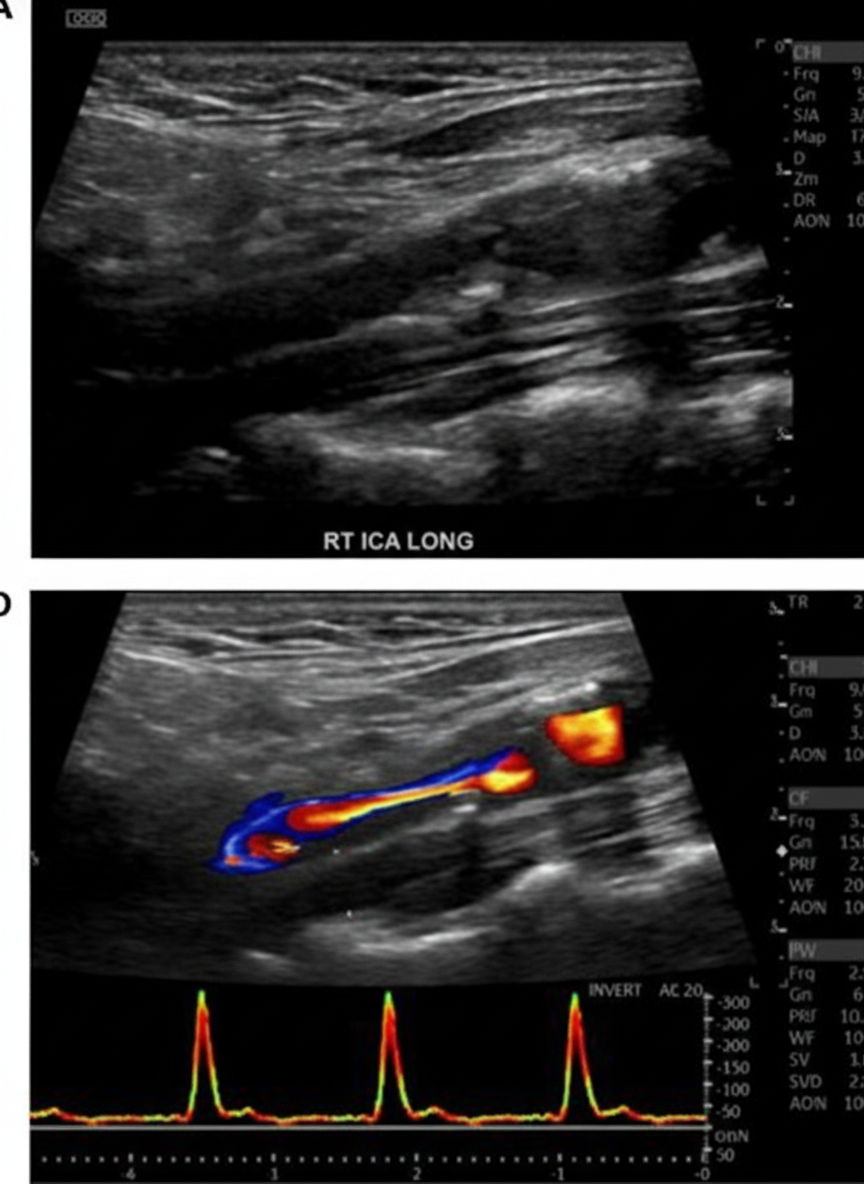

Explanation: ***Carotid endarterectomy*** - The image depicts **carotid artery stenosis**, likely from **atherosclerosis**, in a patient who received neck irradiation. **Carotid endarterectomy** is the gold standard for symptomatic or severe asymptomatic carotid stenosis. - Neck irradiation often causes **accelerated atherosclerosis** and fibrosis, making the vessels brittle and prone to complications with endovascular procedures like stenting. *Low dose Aspirin* - **Low-dose aspirin** is an antiplatelet medication and plays a role in the **secondary prevention** of atherosclerotic events, but it is insufficient as a primary management for advanced, symptomatic carotid stenosis requiring revascularization. - While important for reducing the risk of stroke, it does not directly address the **physical obstruction** caused by severe stenosis. *Carotid angioplasty and stenting* - **Carotid angioplasty and stenting** are generally considered less favorable than endarterectomy in patients with **post-irradiation carotid stenosis** due to reported higher rates of perioperative strokes, restenosis, and cranial nerve injuries. - The **fibrotic and calcified nature** of post-irradiation vessels makes them less amenable to PTA and stenting, increasing procedural risks. *Carotid bypass procedure* - **Carotid bypass** is a more complex surgical procedure generally reserved for situations where the carotid artery is extensively diseased, occluded, or unsuitable for endarterectomy, or if there's a need to bypass a segment following tumor resection. - It is not typically the **first-line treatment** for primary atherosclerotic stenosis amenable to endarterectomy. *Anticoagulation therapy* - **Anticoagulation** (e.g., warfarin, DOACs) is not indicated for the primary management of **carotid artery stenosis**, which is an atherosclerotic obstructive disease rather than a thromboembolic disorder. - Anticoagulation does not address the underlying **stenotic lesion** and may increase bleeding risk, particularly in the perioperative setting if surgical intervention becomes necessary.